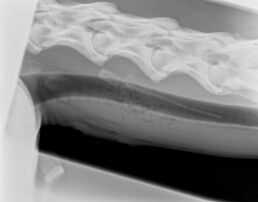

In der röntgenologischen Darstellung des Thorax (Abb.2) konnten keine pathologischen Befunde erhoben werden. Die röntgenologische Darstellung des Halses waren multiple diffuse Gaseinschlüsse im kranialen Drittel des ventralen Halsbereiches (Abb. 3) zu erkennen.

Abb. 3: Hals lateral: multiple diffuse Gaseinschlüsse